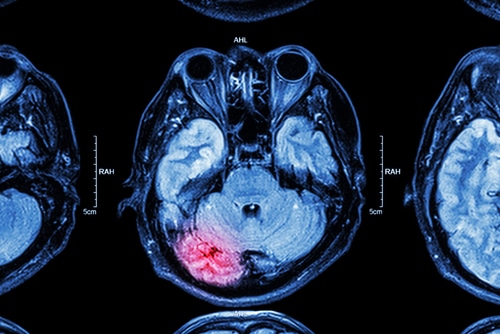

Las lesiones cerebrales traumáticas de moderadas a graves pueden dañar gravemente el cerebro, con heridas potenciales que incluyen hematomas, sangrado y desgarros de tejido. Una lesión cerebral traumática de moderada a grave puede presentar síntomas similares a los síntomas de una lesión cerebral traumática leve, además de convulsiones, convulsiones, entumecimiento, problemas de coordinación, dilatación de las pupilas, líquido en la nariz y los oídos y coma. En general, una lesión cerebral traumática de moderada a grave exhibirá síntomas más elevados en comparación con una lesión leve.

Una lesión cerebral traumática se puede diagnosticar a través de pruebas que examinan la coherencia y la capacidad de movimiento del paciente. Los médicos usan pruebas de imágenes, como una tomografía computarizada o una resonancia magnética, para ver el daño en el cerebro.